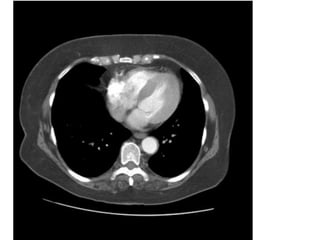

U roán phoåi (P) xaâm laán trung thaát - T4

Haïch trung thaát - N3